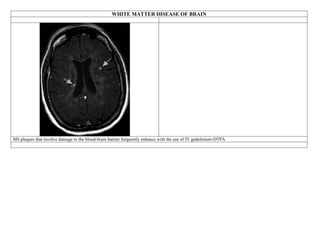

WHITE MATTER DISEASE OF BRAIN

Although the T1-weighted MR images are usually normal, the FLAIR and T2-weighted images demonstrate MS plaques as high–signal

intensity areas. These are most frequently seen in the periventricular white matter, especially around the atrium and the tips of the

anterior and posterior horns of the lateral ventricles (Fig. 5-93A and B). The high–signal-intensity plaques also can be seen in other

white matter areas of the cerebral hemispheres, the brainstem, and even the upper spinal cord. When these lesions are seen in patients

younger than 40 years of age, they tend to be relatively specific for MS (84). In patients more than 50 years of age, the MRI findings of

MS are similar to findings in some aging brains, and correlation with the clinical findings helps establish the diagnosis. Recent

T2-weighted (A) and FLAIR (B) MRI demonstrates the periventricular demyelinating plaques of MS as hyperintense areas (arrows)

adjacent to the anterior horns and atria of the lateral ventricles.

MS plaques that involve damage to the blood-brain barrier frequently enhance with the use of IV gadolinium-DTPA